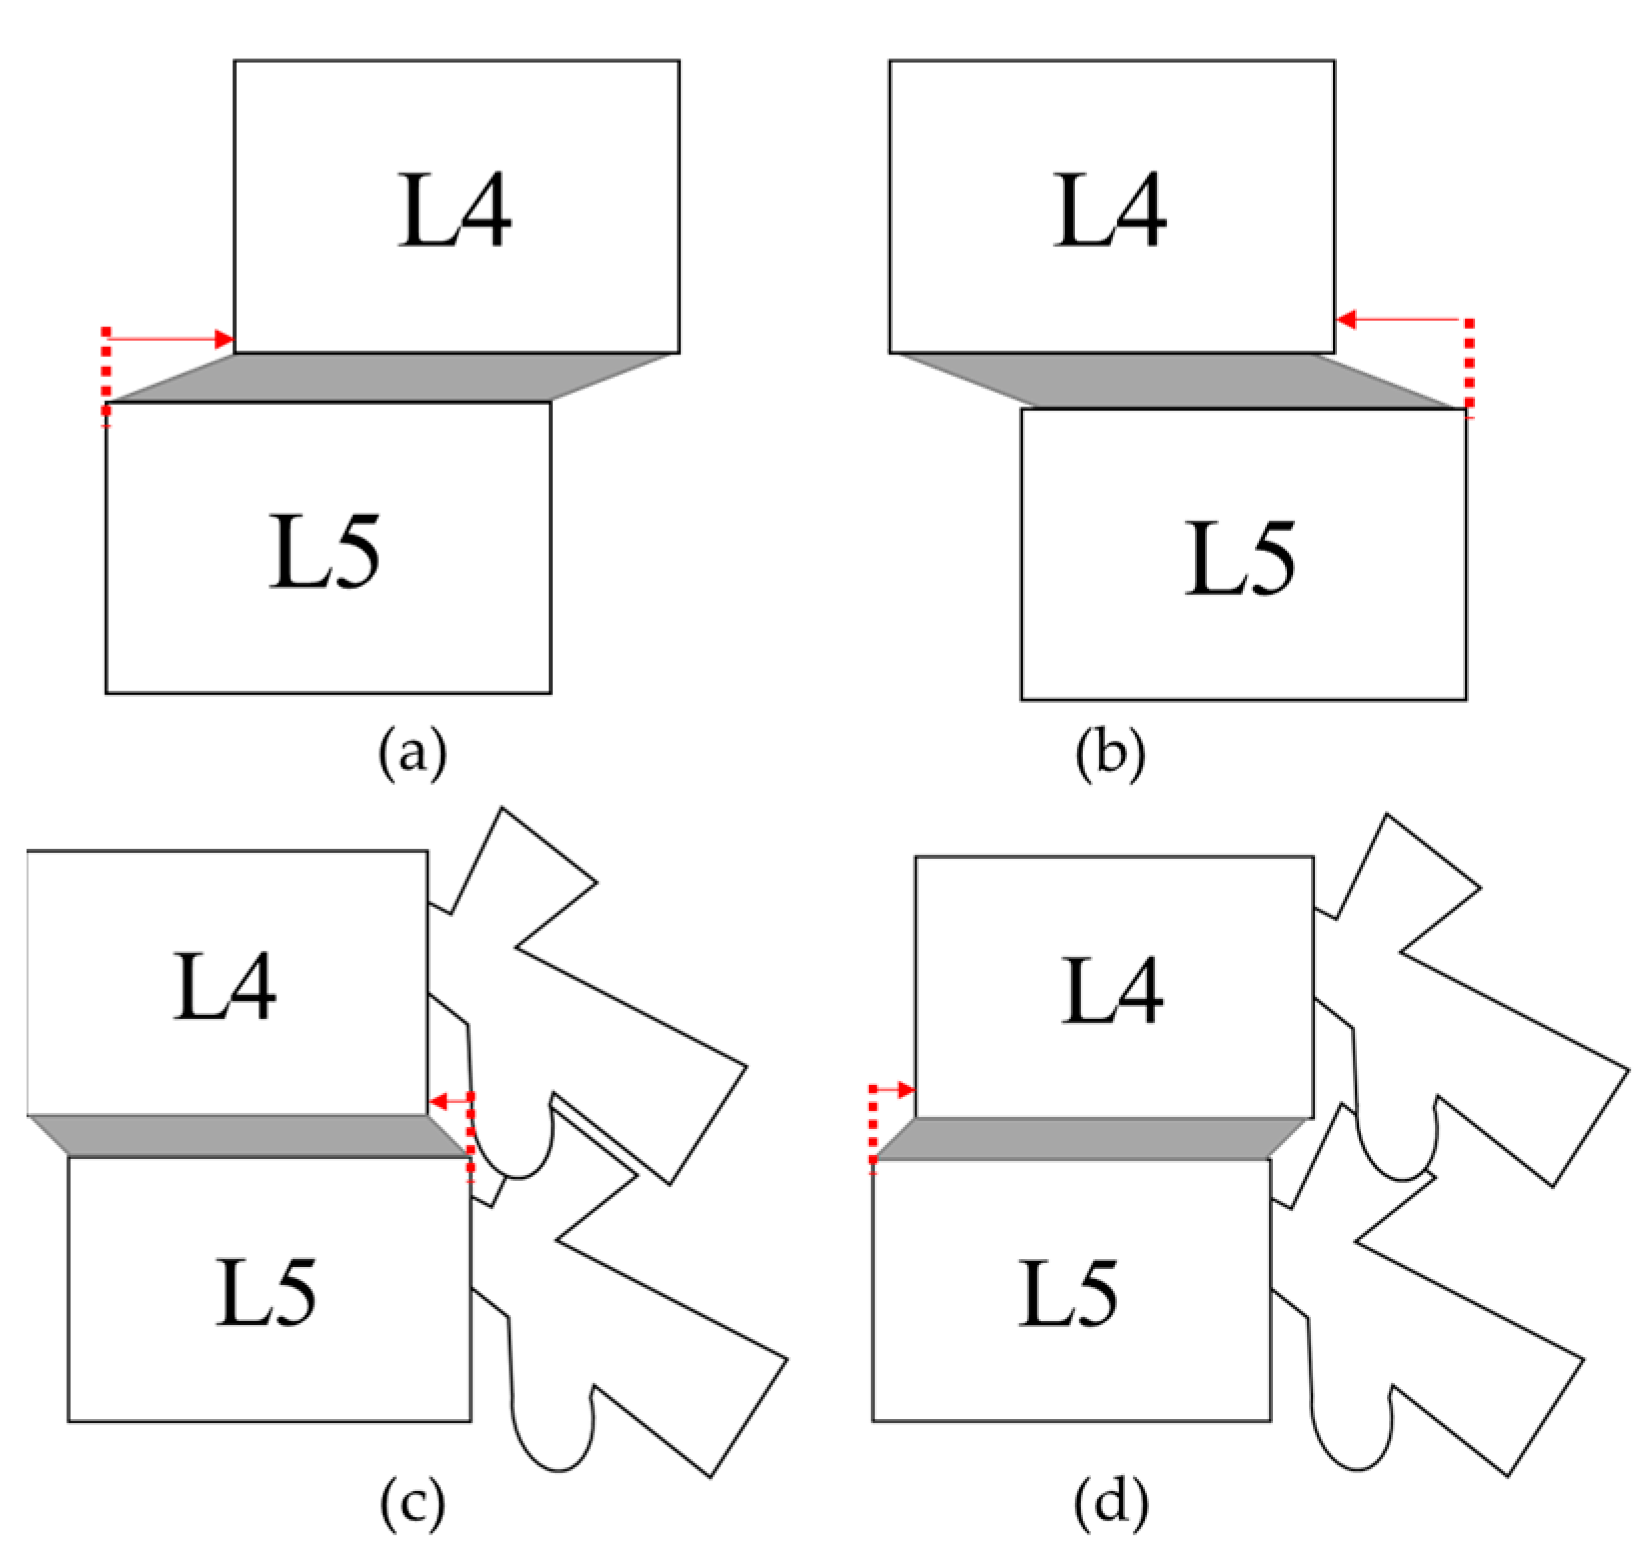

2.2.2. Spondylolisthesis